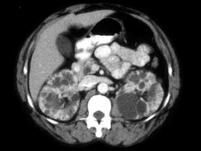

女,35岁,请根据所示图像,选择最可能诊断 ( )A、囊性肾癌B、单纯性肾囊肿C、多发性肾囊肿D、肾癌E、多囊肾

问题 女,35岁,请根据所示图像,选择最可能诊断 ( )

选项 A、囊性肾癌 B、单纯性肾囊肿 C、多发性肾囊肿 D、肾癌 E、多囊肾

答案 E